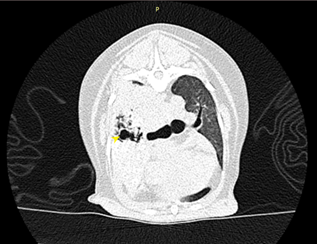

狗狗 肺臟腫瘤 Pulmonary carcinoma

持續數月的咳喘 他院懷疑心臟問題轉診來築心,經由電腦斷層掃描及胸腔採樣

確診為惡性腫瘤,由於腫瘤已經擴散不適合外科手術,主人最後決定使用化療延長壽命